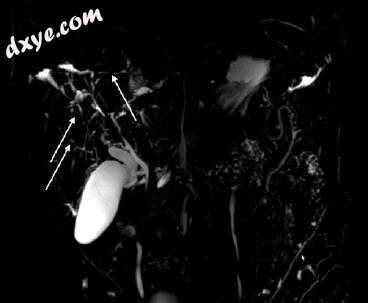

图5.2 25岁男性患者肝移植后慢性胆管炎显示肝内胆管系统有多种结石和淤积,胆管扩张和周围炎症改变,如轴位T2加权脂肪饱和MR图像所见